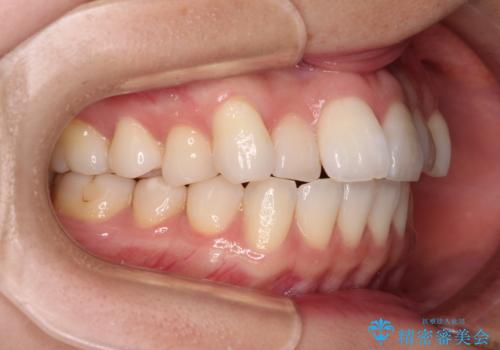

前歯のデコボコと口元の膨らみを治したい ワイヤー装置での非抜歯矯正

- 前歯のデコボコと、上下前歯が接触せずに前に飛び出していることを気にして来院された患者様です。

舌の突出癖が強く、それが原因で上顎歯列全体が前方に突出し、上下前歯が接触できない状態となっていました。